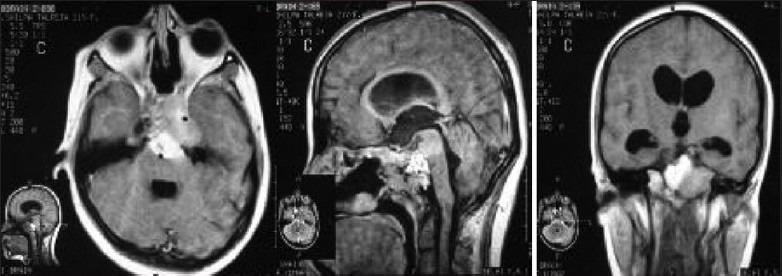

Pediatric suprasellar lesions.

Pediatric brain tumors have always been challenging as well as intriguing in their anatomical, surgical, and postsurgical management-related issues. They are a heterogeneous set of pathologies involving different age groups in childhood and also differ widely from their adult counterparts as far as adjuvant therapies are concerned. Though neurosurgeons across the world are radical in surgery for most of the pediatric tumors, it can often be at the cost of future quality of life in suprasellar tumors. As the time has gone by, the pendulum has swung toward rather conservative and maximal safe surgical resections with adjuvant therapies coming to the forefront. Hence, the aim is to achieve a good quality of life for these children along with a control of tumor growth (rather than cure) and to again tackle the tumors, if required, once these children reach adolescence or adulthood. We have reviewed the literature for different pediatric suprasellar tumors and discussed their current management giving our perspective with illustrative cases.